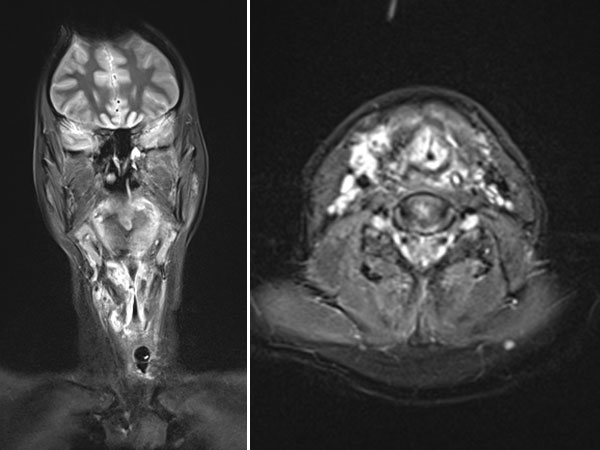

In connection with a systemic infection, now occlusion of the upper airway due to an inflammation-related increase in the swelling of the venous malformation; intubation became necessary. A biopsy was performed. On MRI in the coronal plane (T2-weighted, fat-suppressed), the lesion is very clearly visible as a strongly hyperintense mass. Extensive lesions in the hypopharynx and larynx on both sides.

Transverse T2-weighted, fat-suppressed MRI of the neck also shows extensive, grossly hyperintense (white) portions of the venous malformation on the larynx and neck. These obstruct the upper airway. The endotracheal tube is visible in the center.